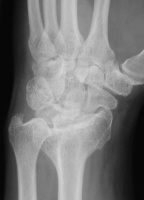

Clinical Example: Radioscapholunate Fusion and Triquetrum excision for Radiocarpal Arthritis

Radioscapholunate fusion is a treatment option for radiocarpal arthritis following distal radius fracture or associated with rheumatoid arthritis. Range of motion is usually less than half of normal following this procedure. Technical modifications to improve range of motion include distal scaphoid excision, or as in this case, triquetrum excision and excision of distal ulnar articular surface to manage ulnolunate abutment. There are a variety of fixation techniques. In this case, crossed Herbert screws were used: dorsal carpal bone to palmar radius and dorsal radius to palmar carpal bone.

Preop, wrist splint tan line, two years after intraarticular distal radius fracture:

Preoperative Xrays: